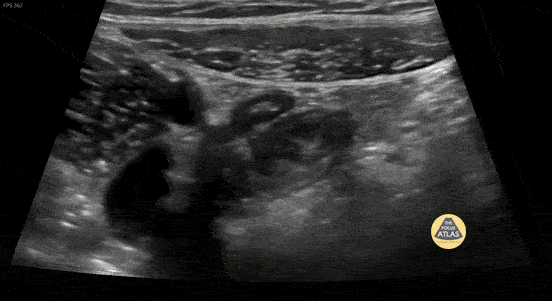

10 y/o with abdominal pain. Normal appendix identified medial to the iliac vessels. Please see other image in series for doppler. Contributor: Elena Chen, MD